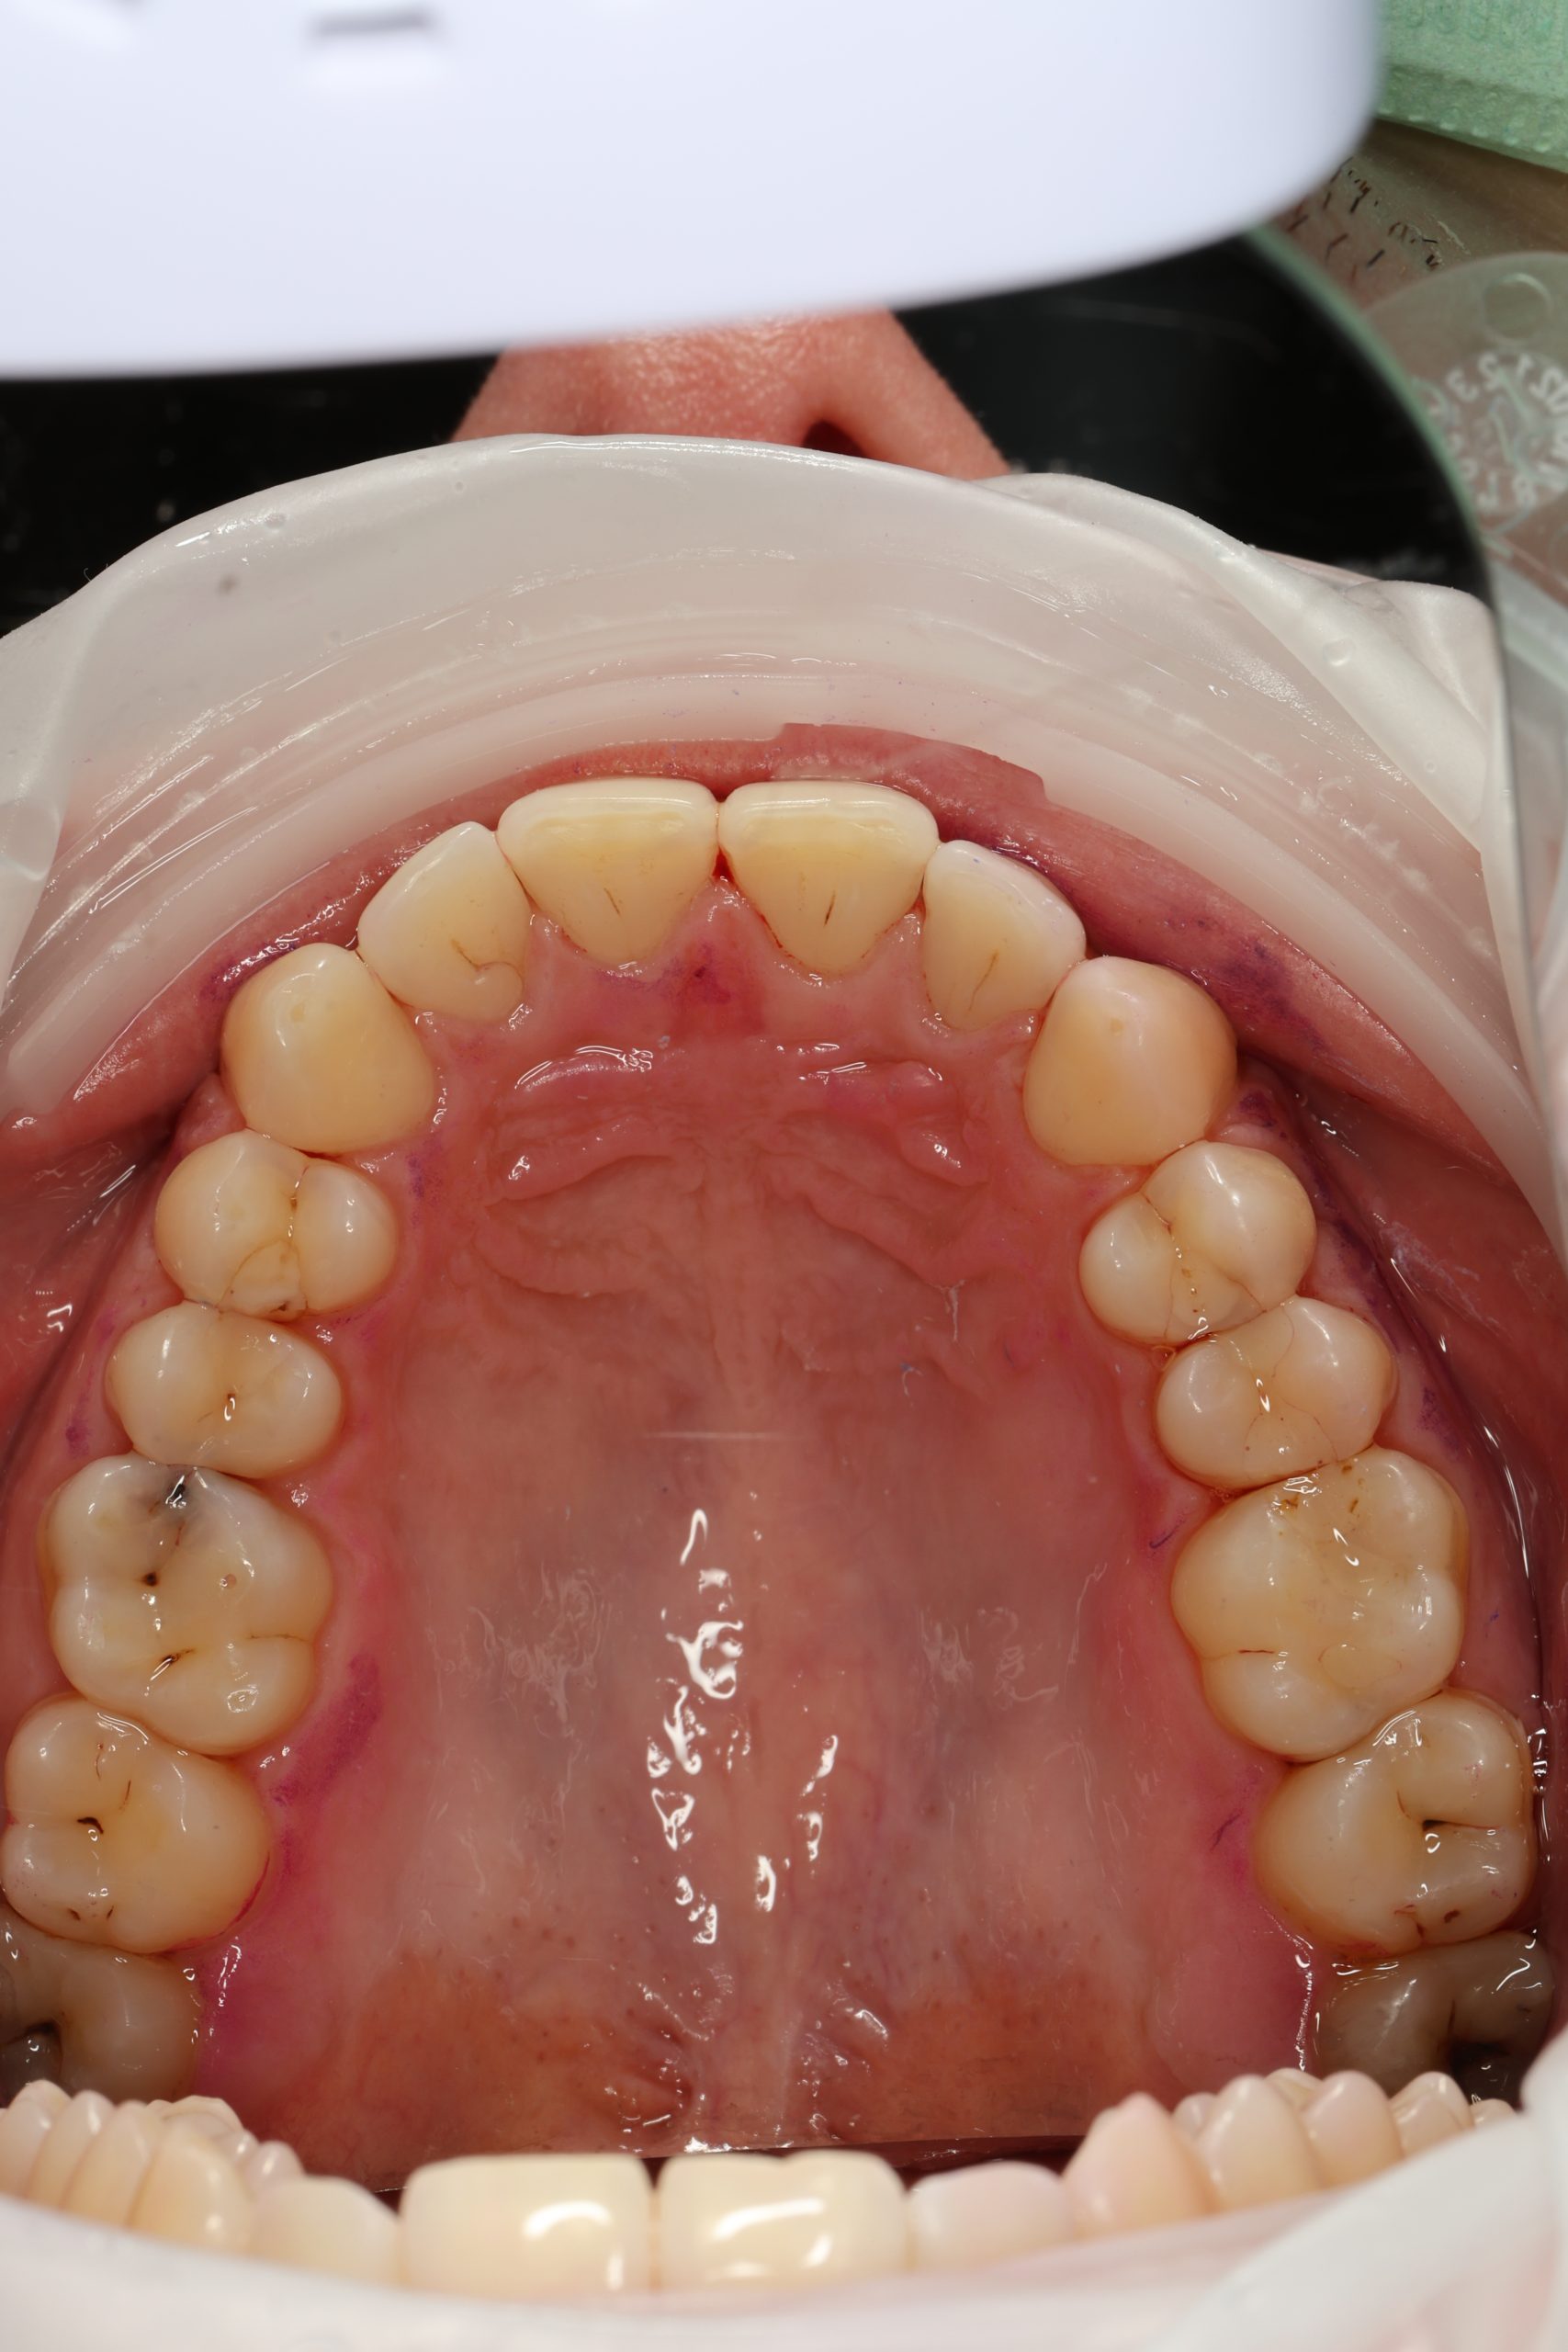

Inside every tooth lies a narrow chamber that contains nerves and blood vessels — the dental pulp. When deep decay, a leaking filling, or trauma allows bacteria to reach this inner space, the pulp becomes inflamed and then infected. The result is pressure, sensitivity, and often an unmistakable throbbing pain.

Our dentists perform root canal therapy every day. Complex anatomy and retreatments are routine. Each difficult case is planned by our senior clinician to ensure the right strategy from the start. - Microscope precision and isolation

Under bright magnified light, a tiny opening is created and every canal located — even the hidden ones that often cause failures elsewhere. - Cleaning and shaping